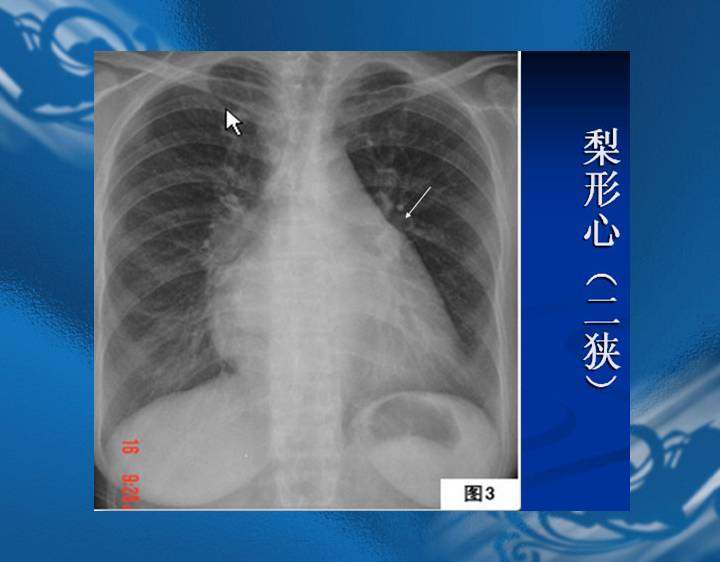

执业医师资格考试“实践技能”影像学辅导资料